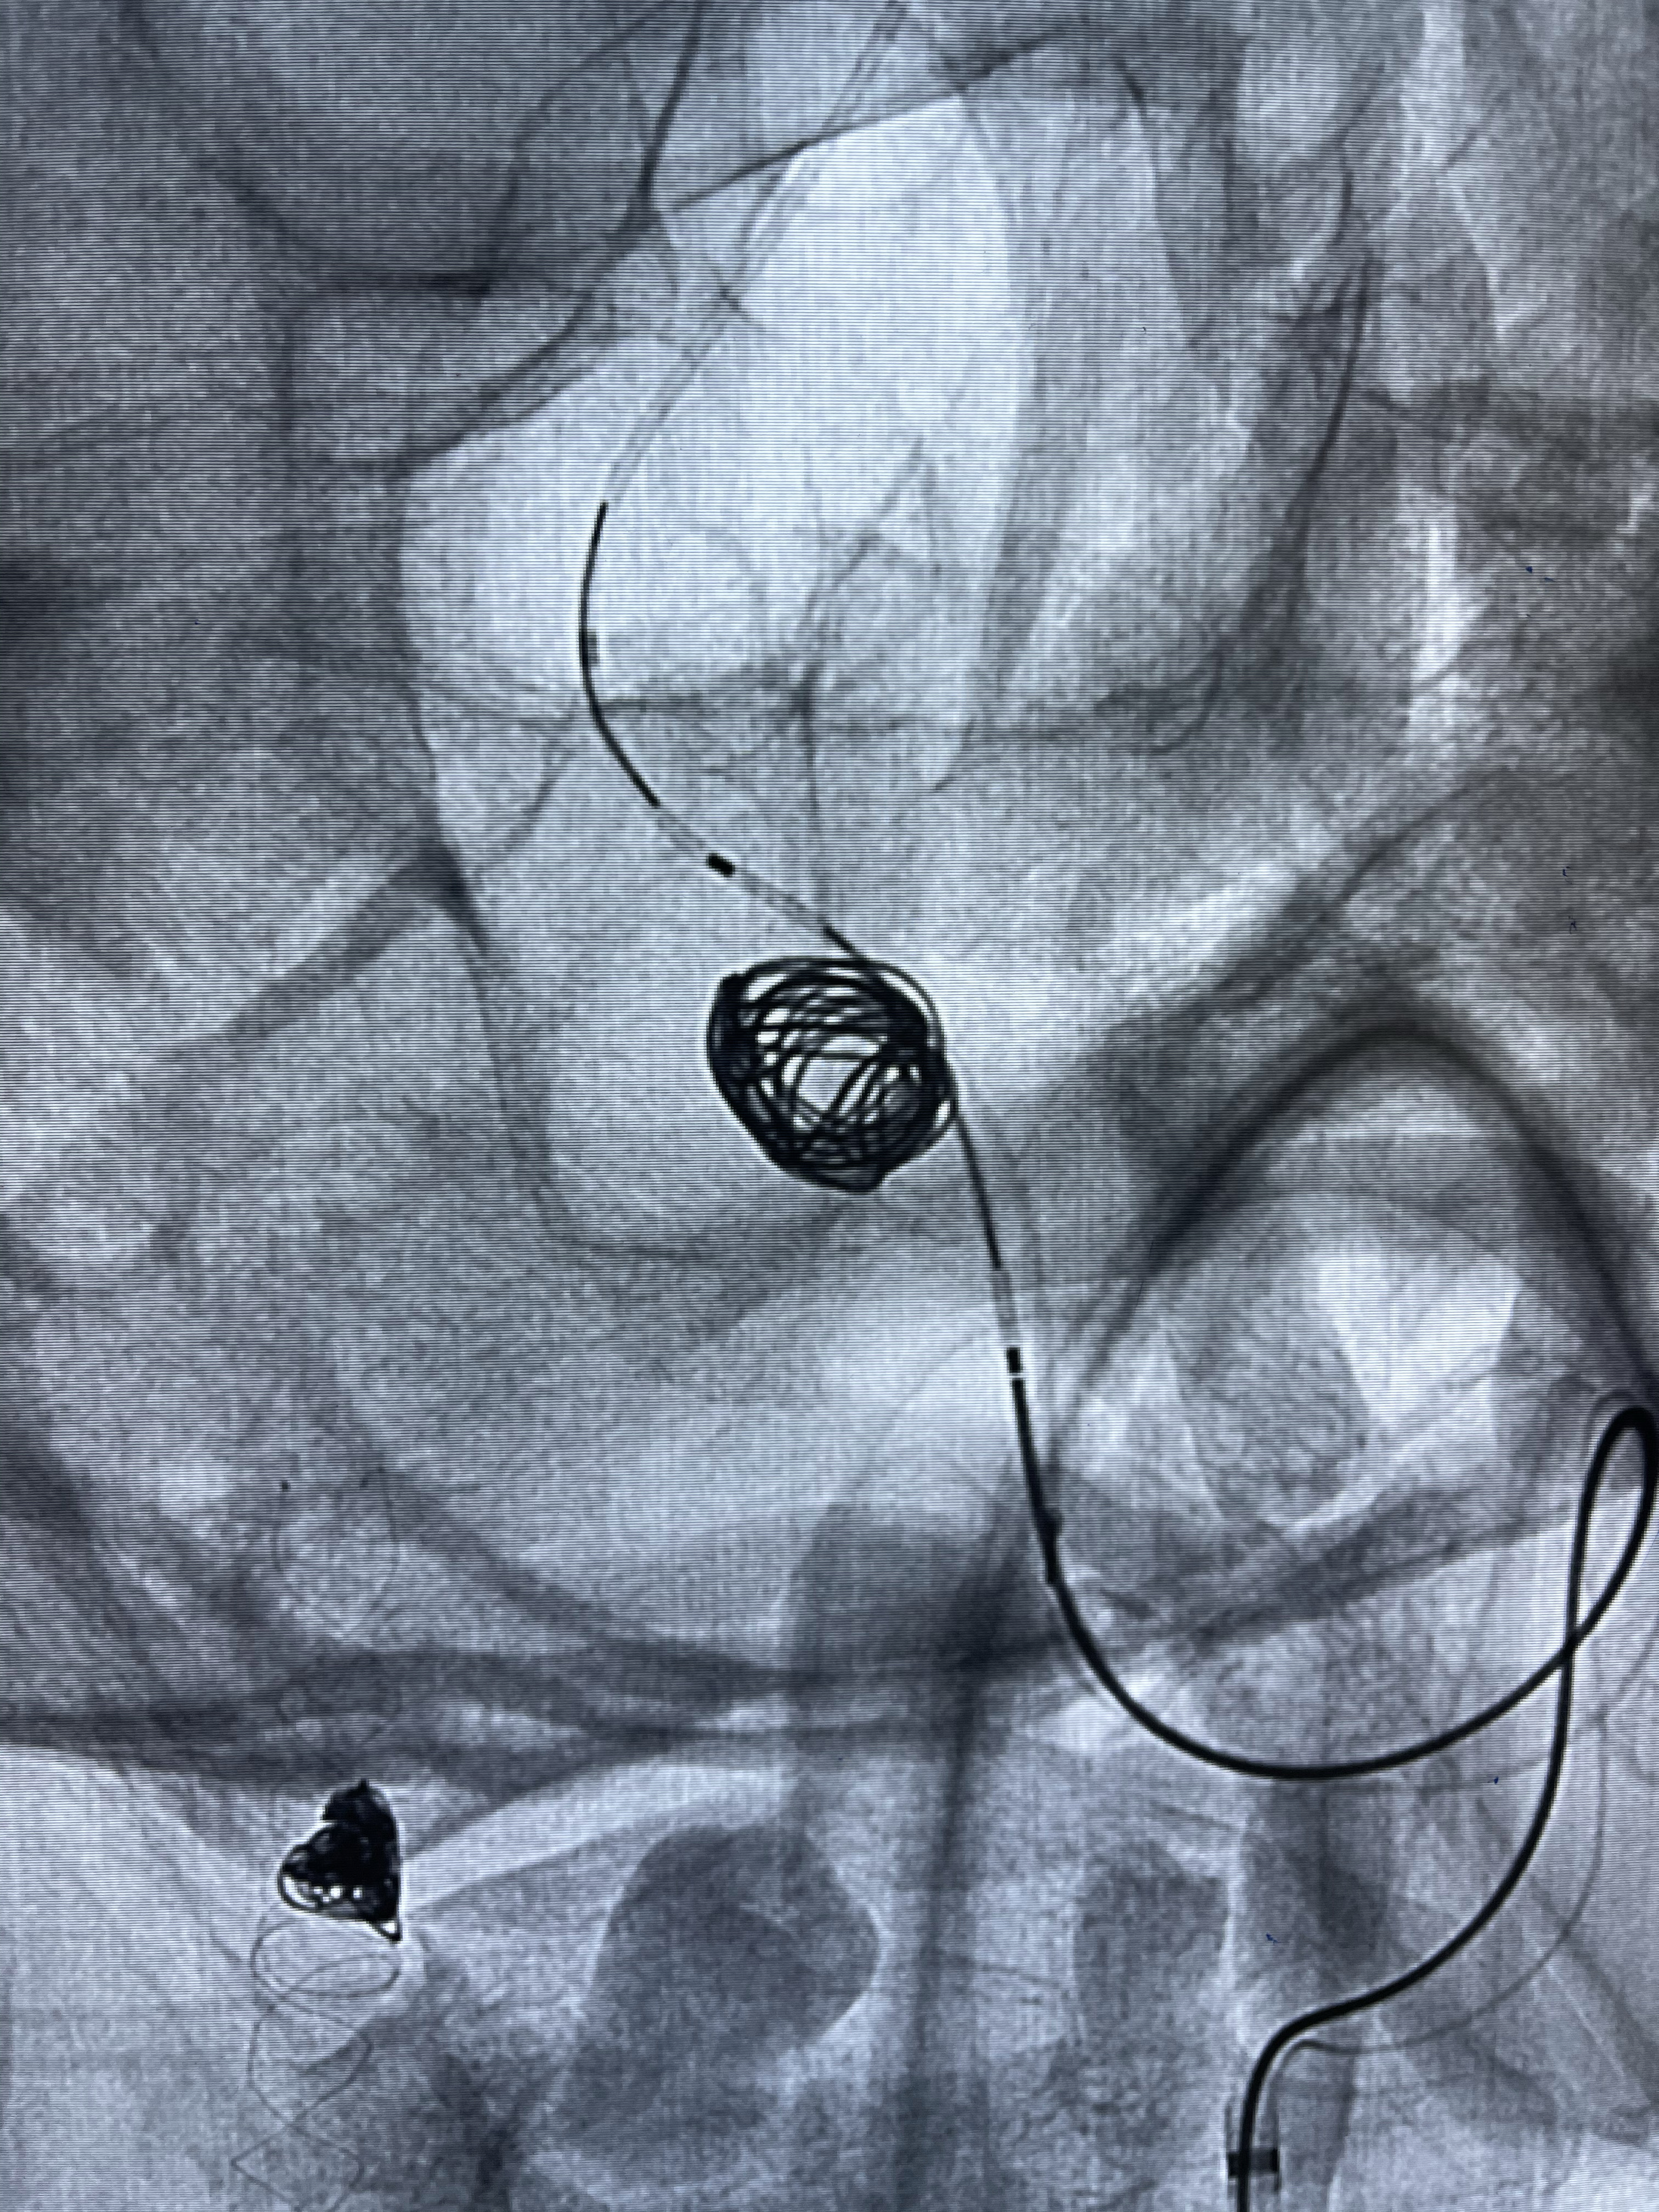

Echelon10 45°角微导管塑形后到位

8mm-40cm微弹簧圈成篮

即刻造影